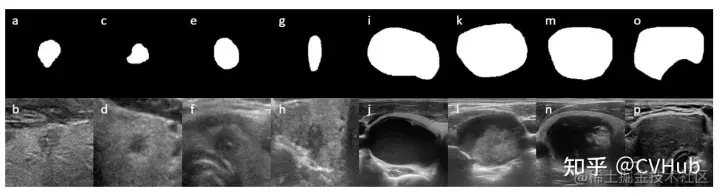

当训练第二个网络时,我们将GT得到的结节ROI展开,然后将扩大的ROI中的图像裁剪出来,并将其大小调整为512×512像素,以供第二个网络使用。我们观察到,在大多数病例中,大结节一般边界清楚,而且小结节的灰度值与周围正常的甲状腺组织的灰度值差异较大(如上图所示)。因此,背景信息(结节周围组织)对于小结节的分割具有重要意义。如下图所示,在预处理后大小为256×256像素的图像中,首先得到结节感兴趣区域的最小外平方,然后若正方形边长n大于80,则外扩m为20,否则m为30。